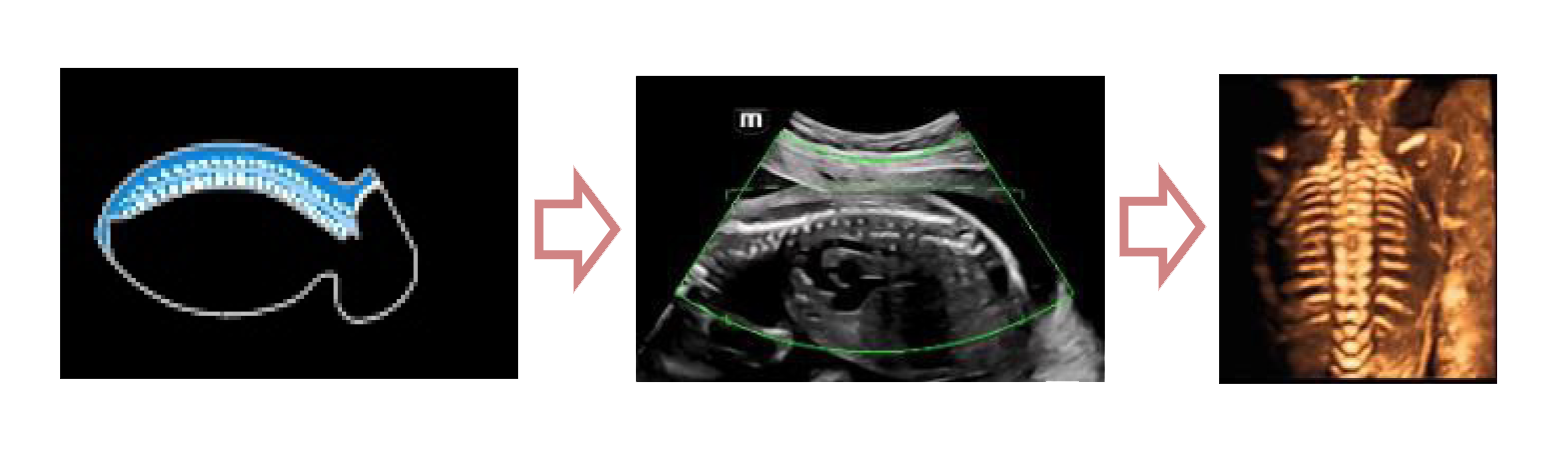

С легкостью получайте потрясающие 3D изображения позвоночника плода

- Автоматическое распознавание анатомии позвоночника плода

- Автоматическая подстройка зоны интереса и положения до оптимального

- Автоматический определение параметров рендеринга позвоночника